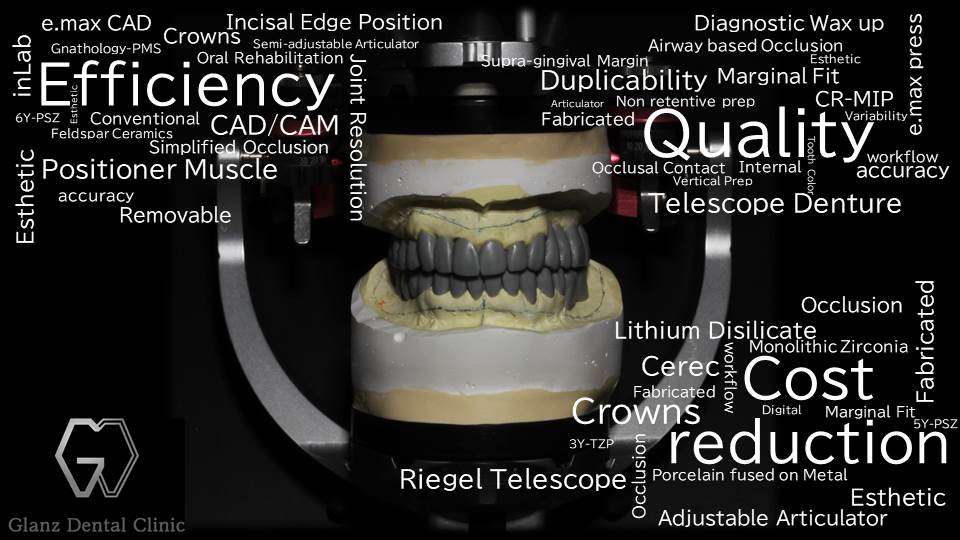

写真は、歯周病で長く伸びてしまった歯ばかりになってしまった患者様のテレスコープ義歯です。「はめ込み式の入れ歯」である「レジリエンツ テレスコープ」で治療させて頂きました。バネ式の入れ歯ではありませんので、一度得られた歯並び、咬み合わせ、装着感には長期に渡って変化がありません。

次世代型CADCAMデジタルテクノロジーを駆使した最新式のテレスコープ義歯の専門治療が受けられるのは「グランツ歯科クリニック」です。

※画像の治療:補綴専門医である院長 岡本の治療となります。